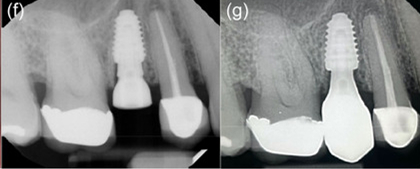

Minimally invasive removal of fractured premolar and placement of immediate implant (Megagen Anyridge) without osteotomy on Patient 3: (a) Fractured non‐restorable premolar. (b) Prepless immediate implant. (c) Cover screw placed to accommodate grafting with cortical cancellous allograft. (d) Anatomical healing abutment placed on the day of surgery. (e) Final monolithic Zr restoration. (f) Peri‐apical radiograph of day of surgery with anatomical healing abutment. (g) Peri‐apical radiograph with definitive restoration at 12 months.